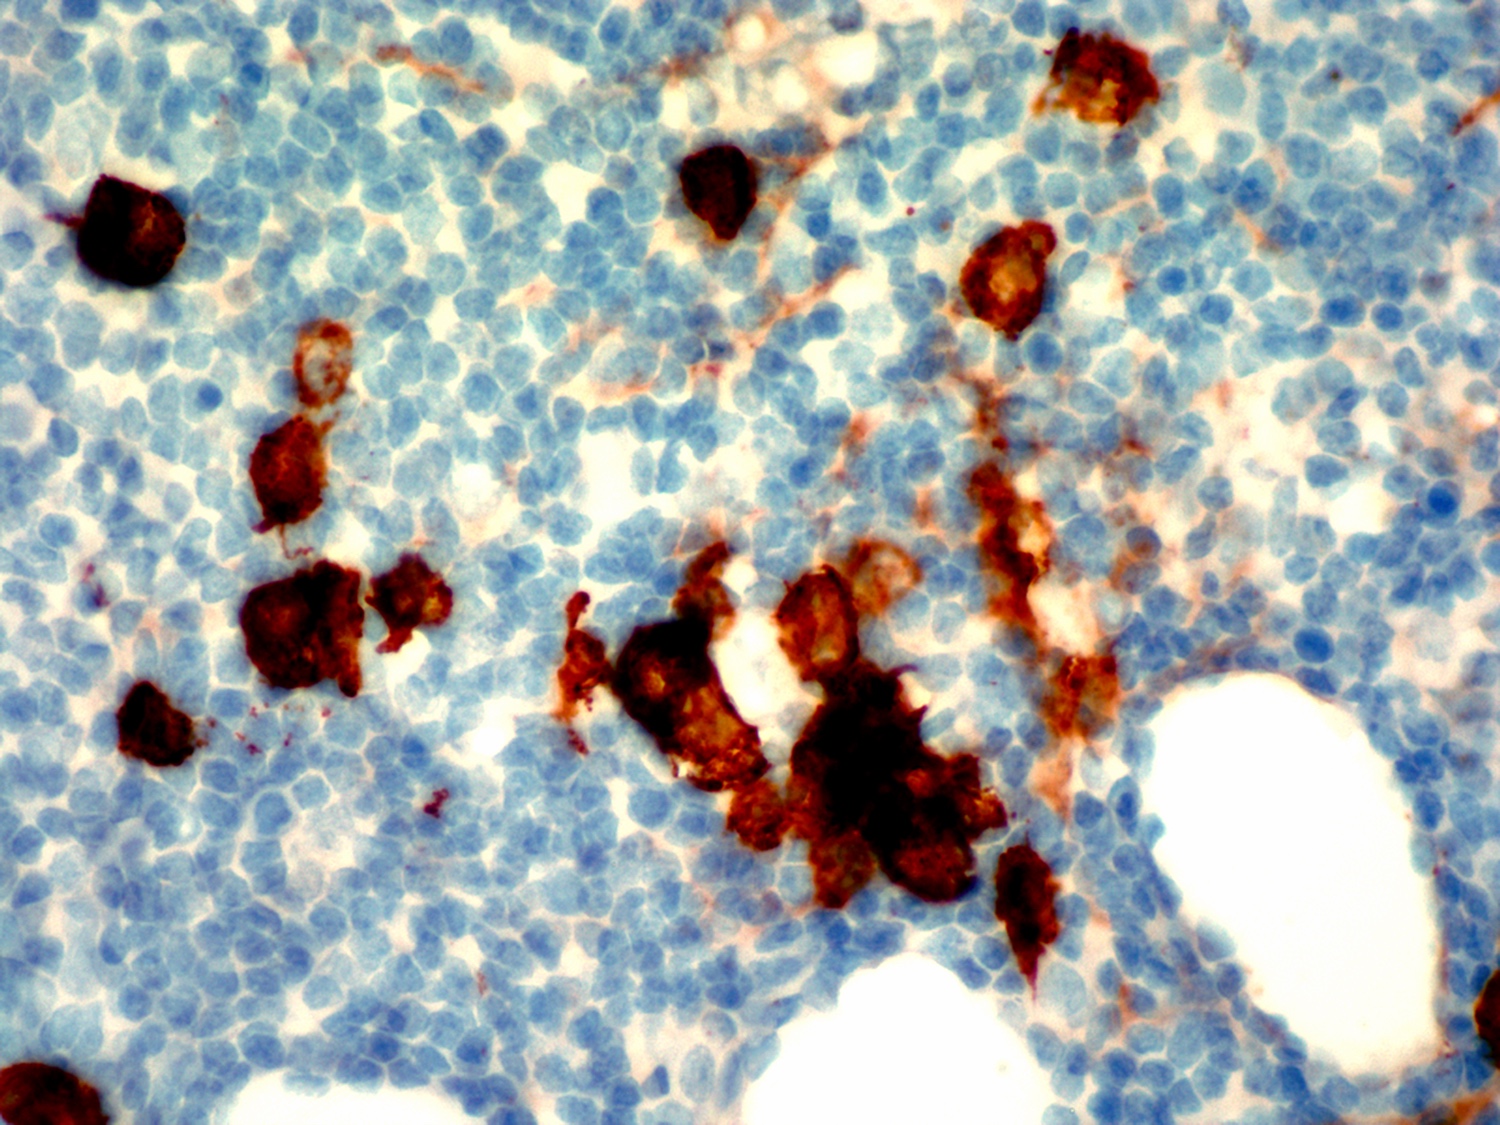

Microscopic (histologic) images

Contributed by Ling Zhang, M.D.

Positive stains